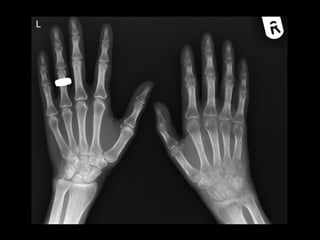

Radiologic findings ofRadiologic findings of

HYPERPARATHYROIDISMHYPERPARATHYROIDISM

• Subperiosteal resorption - M/C

– Usually occurs in the hands and feet.

– M/C affected site: radial aspects of the middle phalanges.

– Acro-osteolysis or phalangeal tufts resoption may also be

present.

AP radiograph of the hand in a 66-year-old woman with primary hyperparathyroidism owing to parathyroid adenoma shows subperiosteal bone

resorption ( arrows) along the radial aspect of 2nd, 3rd, and 4th middle phalanges.